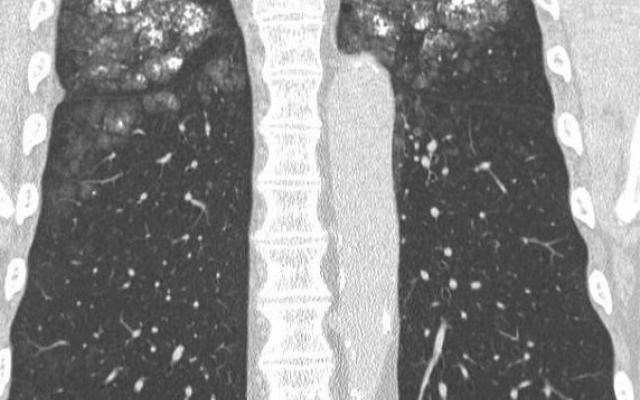

Farmacologische beïnvloeding van kortademigheid door inspanning bij kinderen met CARA